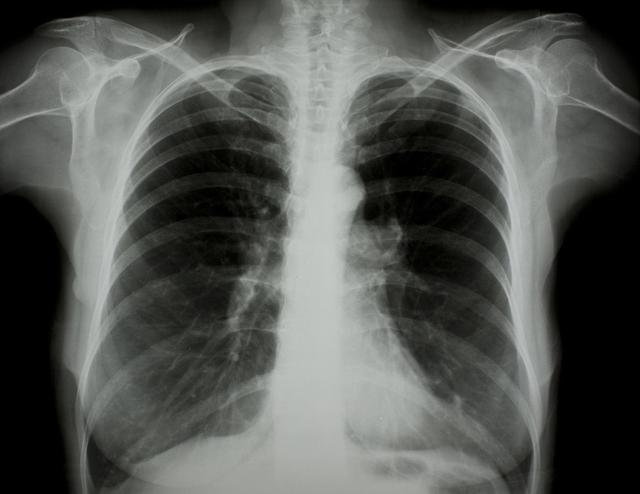

涪陵地區(qū)最新肺炎情況顯示,疫情形勢(shì)嚴(yán)峻。目前,當(dāng)?shù)卣歪t(yī)療部門(mén)正在積極應(yīng)對(duì),采取一系列措施控制疫情傳播。具體感染人數(shù)、癥狀表現(xiàn)、疫苗接種情況等仍在持續(xù)更新中。請(qǐng)廣大市民密切關(guān)注官方發(fā)布的信息,做好個(gè)人防護(hù),共同抗擊疫情。涪陵地區(qū)肺炎疫情嚴(yán)峻,政府積極應(yīng)對(duì),請(qǐng)市民關(guān)注官方信息,加強(qiáng)個(gè)人防護(hù)。

據(jù)最新官方數(shù)據(jù)顯示,涪陵地區(qū)肺炎病例數(shù)量令人擔(dān)憂(yōu),截至目前,涪陵地區(qū)累計(jì)確診肺炎病例XX例,疑似病例XX例,請(qǐng)大家務(wù)必提高警惕,不可掉以輕心。